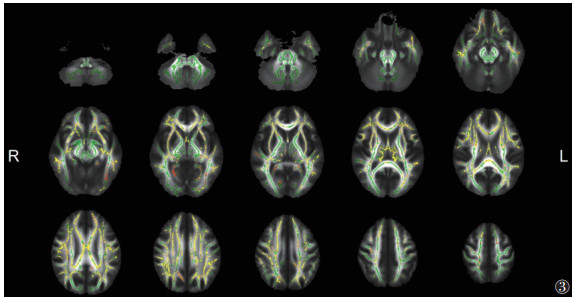

与HC组相比,ITB组脑白质的FA广泛降低、MD升高更广泛(P<0.05,TFCE和FWE校正)(图 2,3)。其中胼胝体体部、胼胝体压部、双侧前放射冠等的FA和MD同时改变(图 4)。

| 注:与HC组相比,ITB组脑白质MD升高的区域显示为暖色(P<0.05,TFCE和FWE校正)。脑白质骨架显示为绿色。L,左;R,右 图 3 ITB组与HC组MD的差异 |